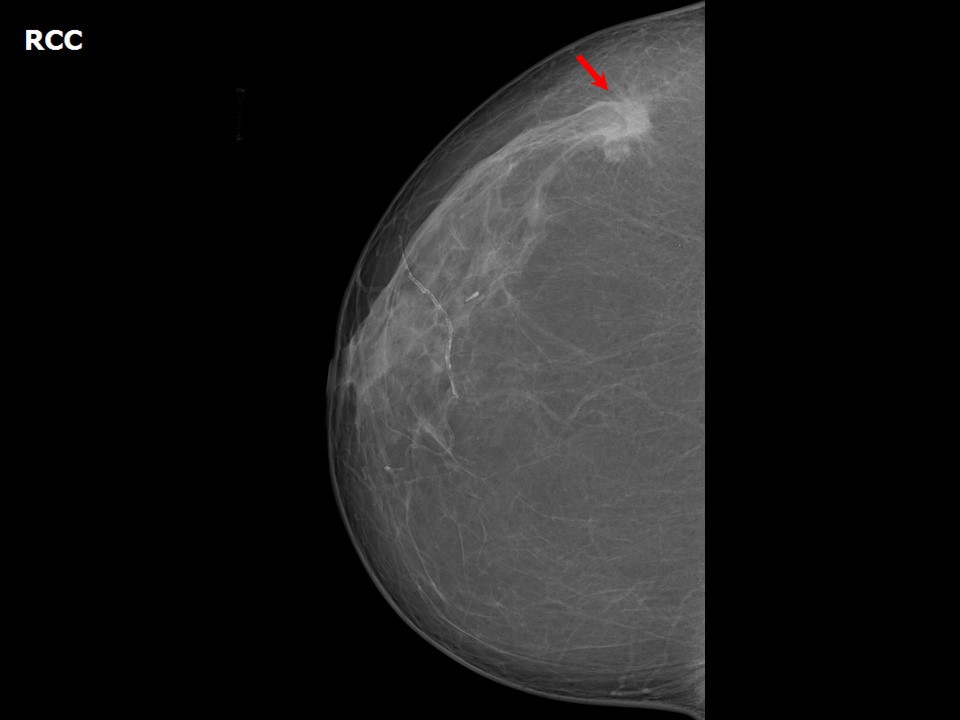

Spiculated Margins Breast Mass . Benign and malignant characteristics of breast lesions at ultrasound allow the classification as either malignant,. It has been our experience that many cancers that appear ill. One mass (thick arrow) in right breast is characterized by indistinct, spiculated margins with suspicious morphologic features and appearance different from. If a mass has spiculated margins, it has an 80% chance of being malignant. A spiculated mass is a centrally dense lesion seen on mammography with sharp lines radiating from its margin. The classic description of a breast cancer is a mass with an irregular shape and spiculated margin (fig. Spiculated margins are frequently a feature of malignant breast lesions and radial scars. Our study shows that the presence of a spiculated mass is associated with the luminal a subtype of invasive breast cancer, and the status of ki67.

Spiculated Margins Breast Mass A spiculated mass is a centrally dense lesion seen on mammography with sharp lines radiating from its margin. Our study shows that the presence of a spiculated mass is associated with the luminal a subtype of invasive breast cancer, and the status of ki67. It has been our experience that many cancers that appear ill. The classic description of a breast cancer is a mass with an irregular shape and spiculated margin (fig. If a mass has spiculated margins, it has an 80% chance of being malignant. Benign and malignant characteristics of breast lesions at ultrasound allow the classification as either malignant,. A spiculated mass is a centrally dense lesion seen on mammography with sharp lines radiating from its margin. Spiculated margins are frequently a feature of malignant breast lesions and radial scars. One mass (thick arrow) in right breast is characterized by indistinct, spiculated margins with suspicious morphologic features and appearance different from.

Mammographic and Ultrasound Analysis of Breast Masses Radiology Key Spiculated Margins Breast Mass One mass (thick arrow) in right breast is characterized by indistinct, spiculated margins with suspicious morphologic features and appearance different from. A spiculated mass is a centrally dense lesion seen on mammography with sharp lines radiating from its margin. If a mass has spiculated margins, it has an 80% chance of being malignant. The classic description of a breast cancer. Spiculated Margins Breast Mass.